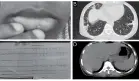

La progresión de los hallazgos radiológicos ofreció pistas diagnósticas retrospectivamente importantes:

Primera radiografía: Neumonía multifocal predominantemente izquierda

Segunda evaluación: Enfermedad intersticial bilateral con lesiones cavitarias en lóbulo superior izquierdo

TC de tórax: Confirmación de cavitación (característica de reactivación tuberculosa) y derrames pleural y pericárdico